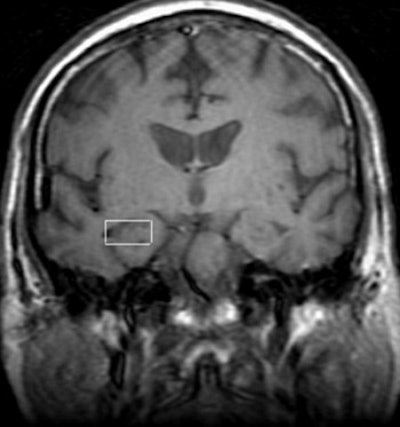

"We acquired single-voxel proton data in three areas of interest," said Caserta, who is an associate professor in the department of psychiatry at the University of Chicago. "We wanted to use this research tool just to look at the function of the brain, and to specifically use spectroscopy to determine levels of N-acetylaspartate (NAA), a marker of neuronal density."

| A 3-tesla proton MR image of a subject with MCI at the level of the mid-hippocampus, with the voxel of interest (2x2x1) placed on the right hippocampus. The left hippocampus was scanned at this level as well. Image courtesy of Dr. Maria Caserta. |

According to the results, the group found distinct and significant differences in levels of NAA. The levels were sharply lower among patients with MCI or probable Alzheimer's disease than with the healthy controls. The effect was especially apparent in the right hippocampus. They found no substantive differences in the posterior cingulate gyrus.

Caserta said the differences in the right and left hippocampal regions were intriguing because they suggested that the beginnings of dementia might originate in the hippocampus even before the appearance of cognitive symptoms.

For example, the NAA/creatine ratio in the right hippocampus was 1.45 for normal controls, 1.12 for those with MCI and 1.18 for patients with early Alzheimer’s disease. In the left hippocampus, the ratio was nearly identical for the controls, 1.46, but declined to 1.33 in those with MCI and 1.21 in the Alzheimer’s disease population.